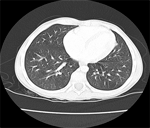

The following is a chest X-ray and CT-scan slide, showing the nice reexpansion of the left lung after few months of the surgery.

![]() Figure 13 |

![]() Figure 14 |